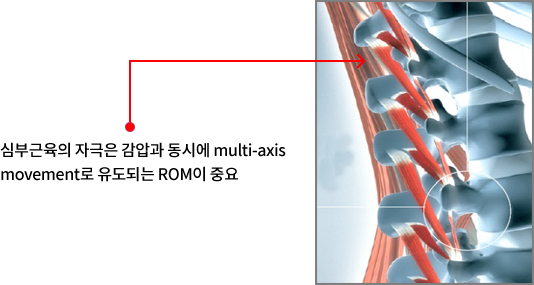

- Spine Column을 지탱하는 Deep Muscle 자극, 재배치(redeploy) 효과 , 근본적인 원인치료

- 목과 허리의 치료 도중 자세(척추관절)의 변화를 유도, 가장 효과적으로 손상된 척추 주변의 근육(심부근육·회전근육)과 관절의 원인적 치료

- 만곡증이 발생하는 골반, 흉추를 기준으로 골반 중심 multi-axis 운동성